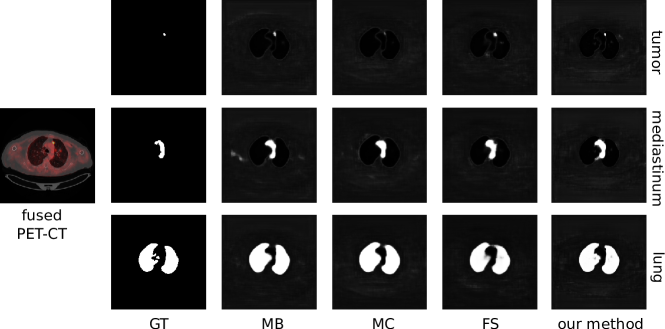

where is the probability that the pixel with observation vector belongs to the region , is the -th element of vector and is the activation corresponding to region . The ‘other’ class (and hence the summation for regions in the denominator of Equation 5) is necessary to formulate the final output of our co-learning CNN as a set of probability maps. The ‘other’ class probability map ensures the sum of probabilities for each pixel has a total of 1 by capturing the probability that a pixel does not belong to any of the ROIs. The use of an additional class to compute the probability of non-ROI regions is a standard formulation that has been used in prior CNN research [73]. Fig. 4 is an example of the probability maps generated for the classes used in our experiments (lung fields, mediastinum, tumors), and the ‘other’ class.

Fig. 5 is a visual comparison of the ROIs detected by our method and by the baselines; a larger version is included as Fig. S3 in the Supplementary Materials. The figure shows that our method consistently detected regions that were a similar size to the ground truth. In contrast, the MC baseline detected fewer pixels (as shown by the tumor region) while the MB and FS baselines detected more pixels than within the region. In particular, the MB CNN gave pixels within the chest wall a high probability of being within the mediastinum.

Fig. 6 is a visual comparison of the segmentation results for a PET-CT image slice with tumors within the lung field as well as in the mediastinum; a larger version is included as Fig. S4 in the Supplementary Materials. The figure shows that our method was able to segment three tumors in different locations across the slice, although they are all slightly over-segmented relative to the GT. In contrast, baseline methods had a tendency to under-segment the tumors.